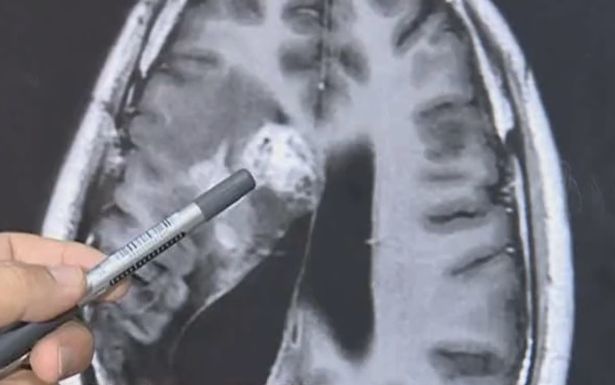

Un homme, Wang Lei, a eu un ténia mangeur de chair de 12 cm de long qui lui avait été retiré de la tête et qui lui rongeait lentement le cerveau depuis 15 ans. Il a commencé à ressentir un engourdissement du côté gauche en 2007 et continue de souffrir de problèmes de santé depuis.

Il a consulté plusieurs spécialistes et a déjà été soigné pour une tumeur maligne au cerveau, alors que les médecins tentaient de déterminer la cause de ses problèmes. Toutefois, l’état de santé du jeune homme a continué de s’aggraver et il a commencé à souffrir de fréquentes crises convulsives.

En 2018, les médecins ont découvert qu’un ver solitaire vivait dans son cerveau et ont conseillé au patient de suivre un traitement non chirurgical, le parasite étant considéré comme une zone à risque.

Malheureusement, le ténia a continué de vivre dans la tête de M. Wang et celui-ci a récemment subi une opération à l’hôpital du Guangdong Sanjiu pour l’enlever.

Après la procédure de deux heures, les médecins ont retiré un parasite de Sparganum mansoni que l’on trouve couramment dans les intestins des chats et des chiens, mais rarement chez l’homme, selon les informations rapportées.